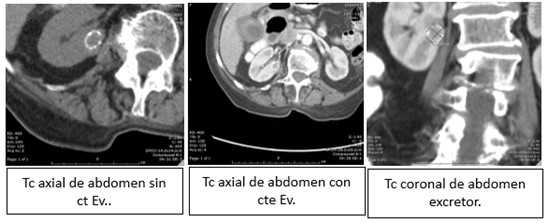

TC: es la técnica de elección para la caracterización de las lesiones renales. El protocolo para el estudio de lesiones renales constará de:

- Estudio basal sin contraste IV: es imprescindible para la valoración del realce en fases posteriores. Asimismo, permite caracterizar las lesiones grasas y la presencia de calcificación.

- Fase córtico-medular: a los 25-70 segundos de la administración del contraste. Es especialmente útil para las lesiones hipervasculares (carcinoma de células claras y metástasis).

- Fase nefrográfica o parenquimatosa: a los 80-120 segundos. Es la fase más eficaz en el estudio de masas renales de menor tamaño.

- Fase excretora (opcional): a partir de los 180 segundos. Útil en sospecha de invasión del aparato excretor y para la planificación quirúrgica en cirugías conservadoras.

La TAC es la técnica de elección para la caracterización de las lesiones renales. El protocolo de TC incluye imágenes sin medio de contraste y con medio de contraste en dos fases:

- Arterial y diferenciación cortico-medular.

- Nefrográfica. La TC nos permite la observación de: